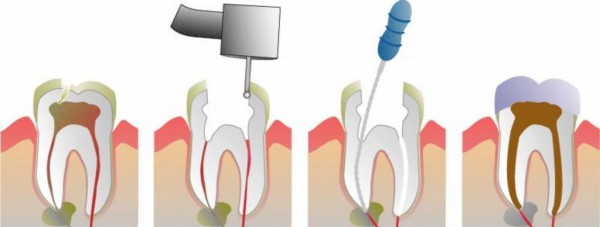

Endodontska terapija podrazumeva tretman unutrašnjosti zuba tj.onog dela u kome je smeštena zubna pulpa, odnosno “zubni živac”. Cilj endodontske terapije je postizanje stanja pri kome će tkiva koja okružuju koren zuba ostati zdrava uprkos činjenici da je “zubni živac” pretrpeo degenerativne promene. Odnosno da ta tkiva ne budu izložena bakterijskoj infekciji koje deluju iz šupljeg prostora u kome se nekada nalazio “zubni živac”.

Najkraće rečeno, lečenje kanala korena podrazumeva mehaničko čišćenje i ispiranje bakterija, raspadnutih organskih sastojaka i bakterijskih toksina koji su preostali nakon propadanja “zubnog živca”. Nakon čišćenja i ispiranja kanala korena sledi njegovo punjenje specijalnim pastama i kočićima kako bi prostor unutar zuba ostao hermetički zatvoren. Na taj način se otklanja mogućnost ponovnog naseljavanja bakterija unutar zuba i ponovnog javljanja zapaljenske reakcije sa svim svojim posledicama.

Terapija se može sprovesti u jednoj seansi, i to najčešće kod jednokorenih zuba(sekutići, očnjaci, donji premolari), ili višeseansno kada se prvo postavi preparat koji umrtvi živac, a nakon desetak dana vrši njegovo uklanjanje i završava kanalna terapija.